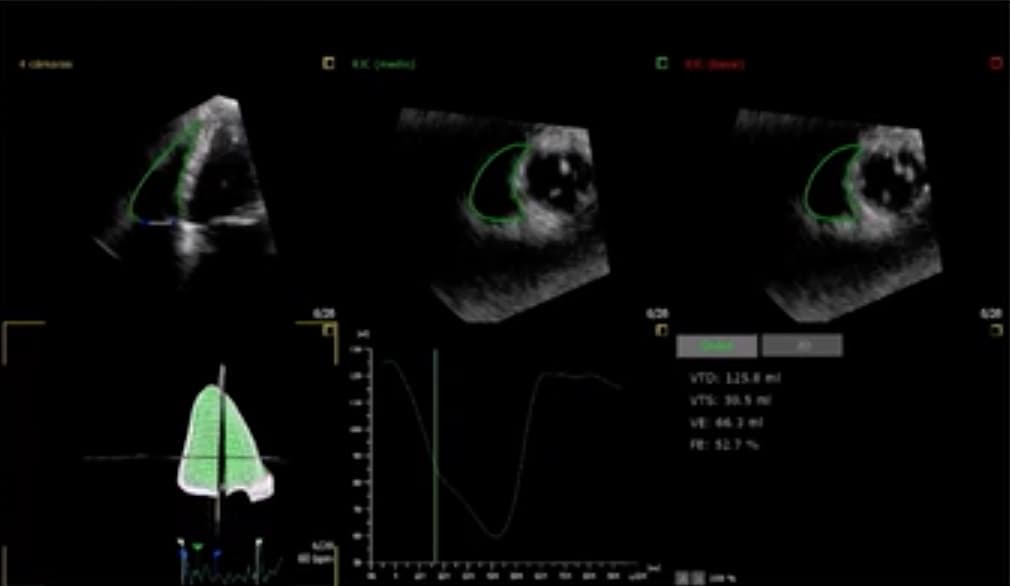

L’IRM fast-tracking est un moyen d’obtenir une meilleure évaluation de la déformation myocardique lors de l’insuffisance cardiaque. Une étude publiée dans la Revue Radiology tente de mieux comprendre la fonction ventriculaire droite dans l’insuffisance cardiaque et identifie la pertinence de l’axe longitudinal pour la prévention de la maladie.